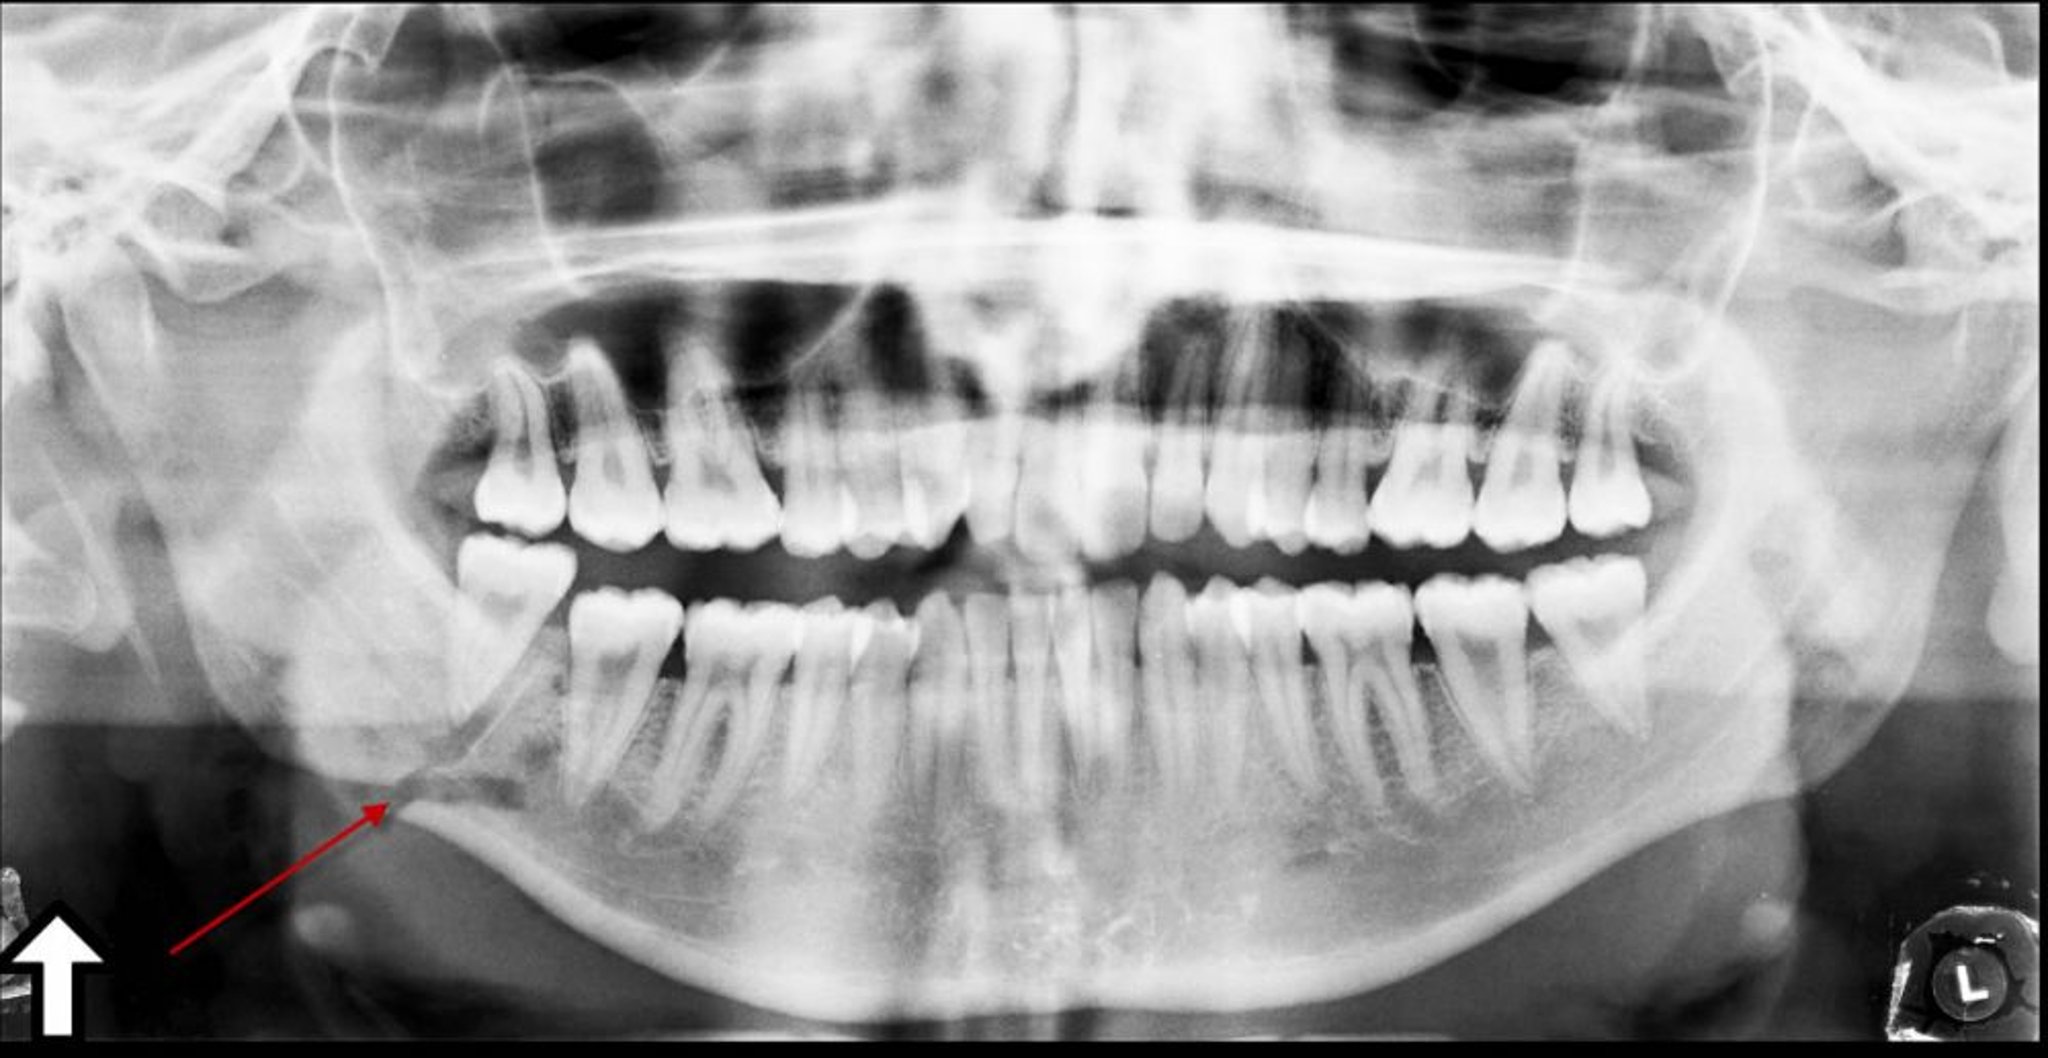

Fracture de l'angle de la mandibule

Cette radiographie panoramique montre une radiotransparence (flèche) au niveau de l'angle de la mandibule, qui représente une fracture.